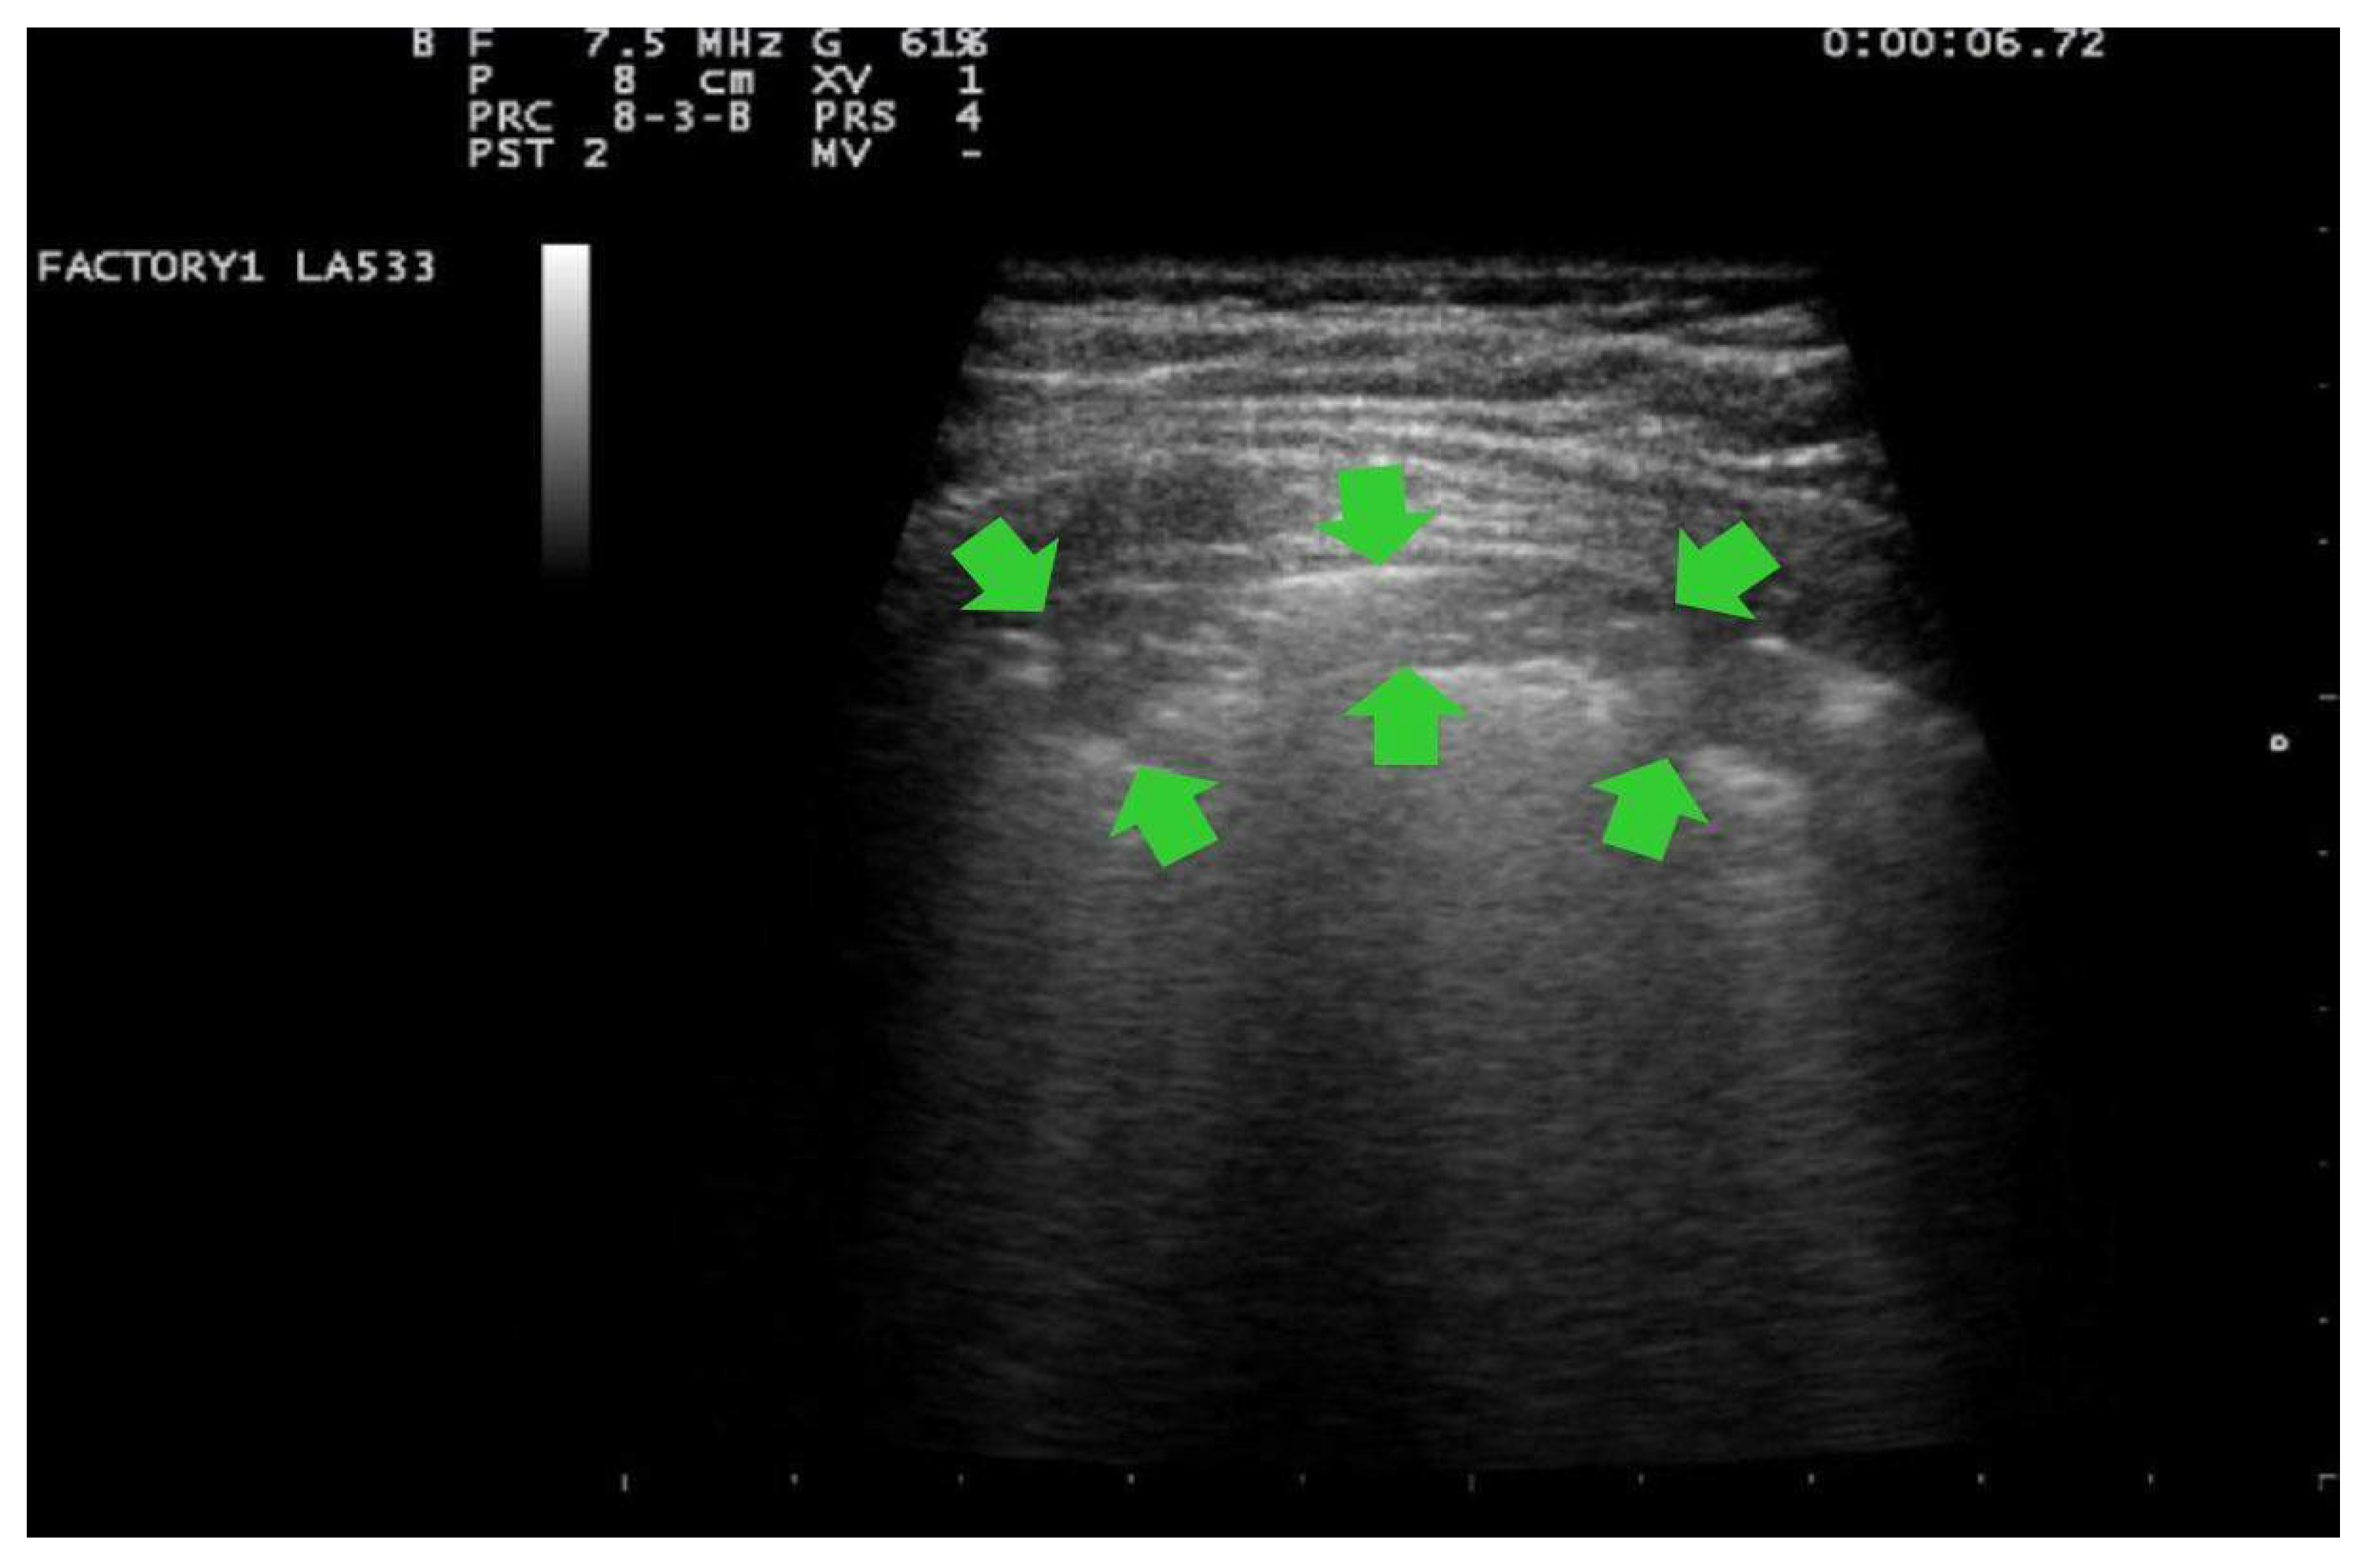

- Score 2:

- confluent B-lines which occupy >50% of the screen without irregularities pleural line. Score 2p: confluent B-lines with a clearly irregular pleural line (Figure 3).